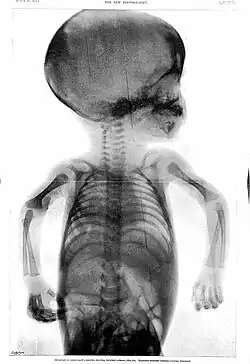

Esse caráter temporário se deve ao fato de que sua função é promover o crescimento dos ossos longos do membro. Trata-se da lâmina epifiasial, um disco cartilaginoso encontrado entre a diáfise e cada uma das duas epífises em ossos longos do indivíduo em fase de crescimento. Ela permite o aumento do comprimento do osso a partir da proliferação desse tecido cartilaginoso, seguida de sua substituição por tecido ósseo. Quando a cartilagem é totalmente ossificada, o aumento de comprimento do osso cessa. As ossificações mais tardias costumam se completar aos 20 anos de idade.[3][18]

Em bebês, nem mesmo as epífises são visualizadas inicialmente, pois têm ossificação mais tardia. Assim, em suas radiografias da mão, os espaços aparentemente vazios são ainda maiores. Só depois que as epífises se ossificam, a porção restante de cartilagem hialina (lâmina epifisial) é observada, entre cada epífise e a diáfise.[19]

Radiografia de mãos adulta e infantil. O bebê nem tem epífises ossificadas, enquanto o adulto até fechou suas lâminas epifisiais. -